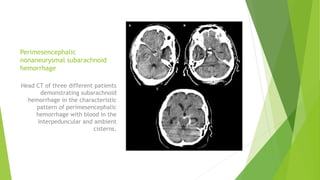

Perimesencephalic

nonaneurysmal subarachnoid

hemorrhage

Head CT of three different patients

demonstrating subarachnoid

hemorrhage in the characteristic

pattern of perimesencephalic

hemorrhage with blood in the

interpeduncular and ambient

cisterns.

Perimesencephalic nonaneurysmal subarachnoid hemorrhage Head CTof three different patients demonstrating subarachnoid hemorrhage in the characteristic pattern of perimesencephalic hemorrhage with blood in the interpeduncular and ambient cisterns.

• #12 •Subarachnoid hemorrhage (SAH) can occur with disruption of small pial vessels and commonly occurs in the sylvian fissures and interpeduncular cisterns. Intraventricular hemorrhage or superficial intracerebral hemorrhage may also extend into the subarachnoid space. &amp;lt;number&amp;gt;